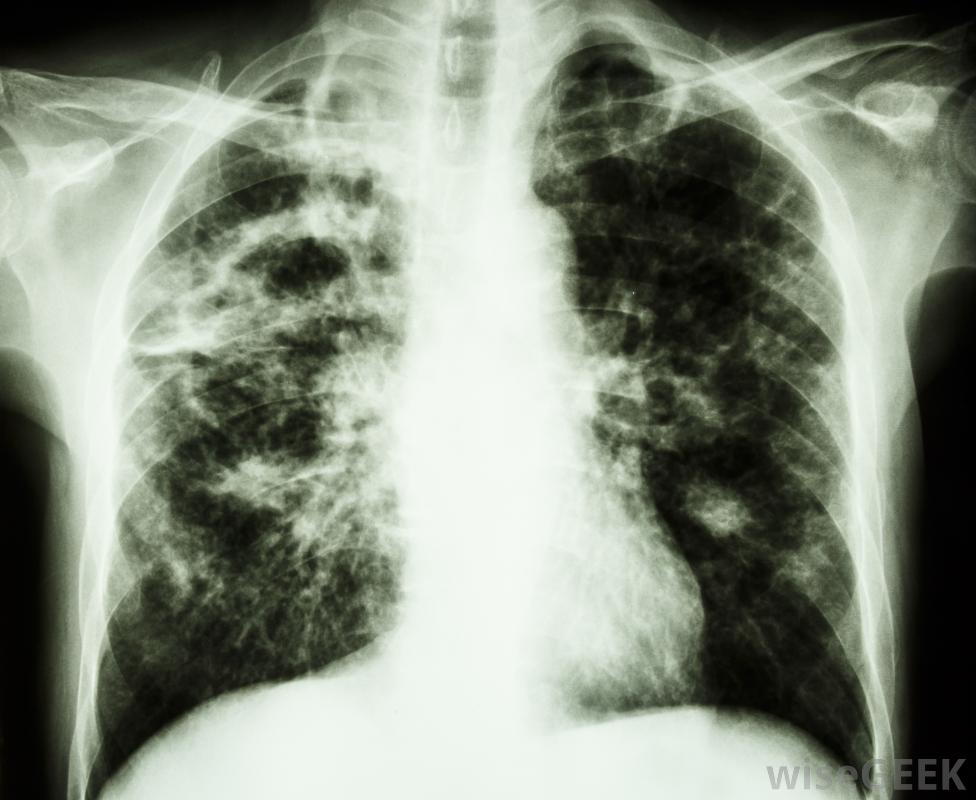

結核病是一種傳染性疾病,可能導致淋巴結腫大。